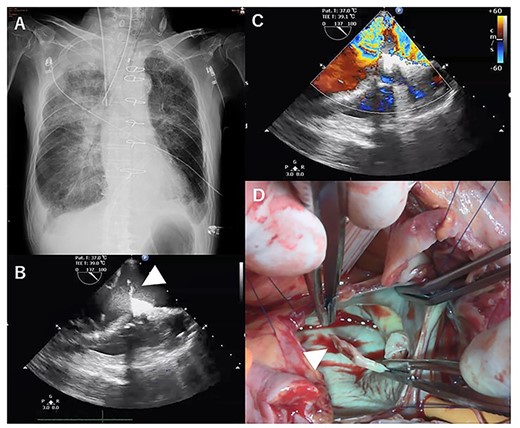

A few hours after treatment, his blood pressure collapsed despite the use of high-dose inotropic support and IABP. On cardiac auscultation, a holosystolic murmur had clearly developed at the left lower sternal border. Since transthoracic echocardiography showed VSP with a left-to-right shunt (Fig. 2A and B), VA-ECMO was started in the ICU and then the patient was transferred to the operating room (OR). Through the median sternotomy, cardiopulmonary bypass was established with aortic and bicaval cannulations, and cardiac arrest was induced with antegrade cold blood cardioplegia. The ventricular septum was approached through the right ventricle parallel to the right posterior descending artery. The VSP was repaired with an extended sandwich patch described by Asai et al. [2] Simultaneous coronary artery bypass grafting to the LAD was also performed using a vein graft. VA-ECMO was removed in the OR, and the IABP was removed on postoperative day (POD) 7. His CHF clearly improved (Fig. 2C), and he was extubated on POD 8.

Transesophageal echocardiography showed a defect with a left-to-right shunt (A). Ventricular septal perforation (VSP) (B). Postoperative chest X-ray (C).